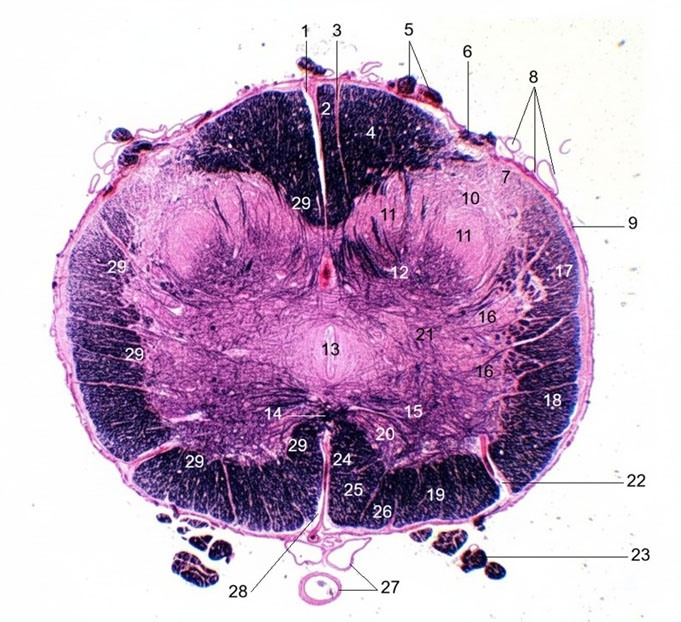

1. Dorsal median sulcus2. Septomarginal fasciculus

3. Dorsal intermediate sulcus

4. Gracile fasciculus

5. Dorsal rootlets

6. Medial root entry zone

7. Dorsolateral tract of Lissauer

8. Subarachnoid vessels

9. Pia matter

10. Dorsal marginal nucleus (Lamina I)

11. Substantia gelatinosa (Lamina II)

12. Nucleus proprius (Lamina III, IV)

13. Central canal with central gray matter

14. Ventral white commissure

15. Ventral horn